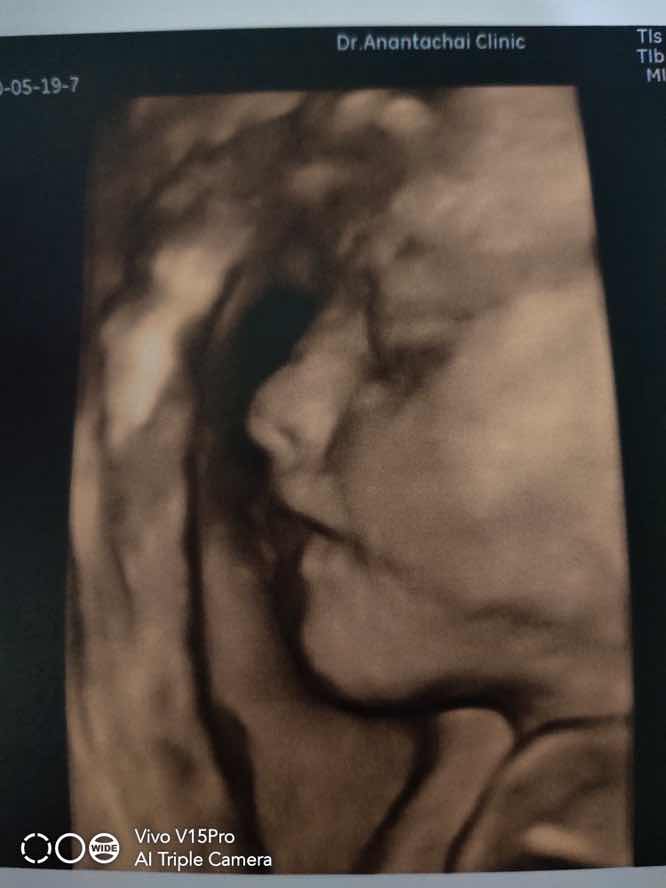

30สิงหาจ้า ลุงหมอ ทั้ง2คลินิคบอกผู้หญิงจ้า